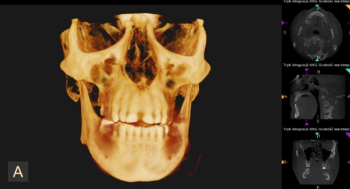

Oferujemy wysokiej jakości badania diagnostyczne, takie jak: RTG punktowe, pantomogram, cefalometria, tomografia CBCT, cyfrowy skan zębów oraz dentystyczny protokół fotograficzny.

Efektywne leczenie stomatologiczne w większości przypadków wymaga dokładnej diagnostyki, opierającej się na zobrazowaniu stanu uzębienia, kości szczęki czy żuchwy. Jednym z popularnych sposobów diagnostyki stomatologicznej jest zdjęcie pantomograficzne, czyli pantomogram. Pozwala ono uzyskać precyzyjny obraz struktur, z odwzorowaniem wszelkich krzywizn i ewentualnych nieprawidłowości. Zaawansowaną diagnostykę zapewnia tomografia komputerowa CBCT, która oferuje obrazowanie w technologii 3D.